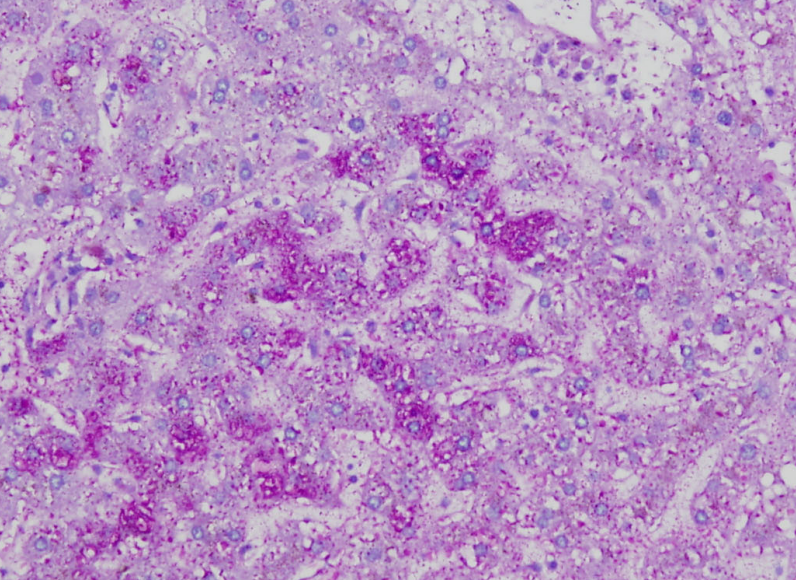

Stains for bile and how does it appear in this stain

H&E- appears brown

Fouchet Hall Bile- olive green